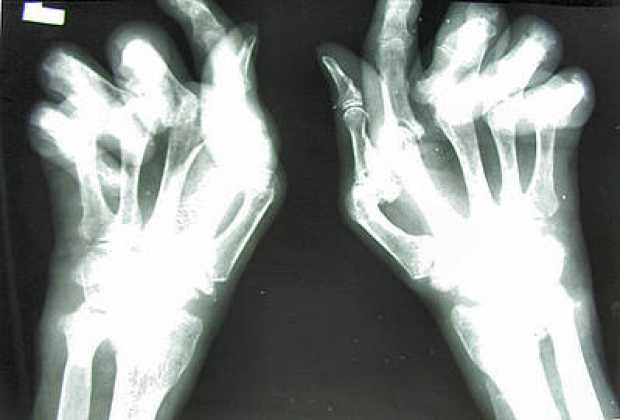

De otra arte, la especialista advierte que un niño con este trastorno, tiene dolor y presenta limitaciones en los movimientos de sus articulaciones afectadas y la persistencia de esa inflamación, altera su morfología definitiva y pueden deformarse sino se trata desde el comienzo.